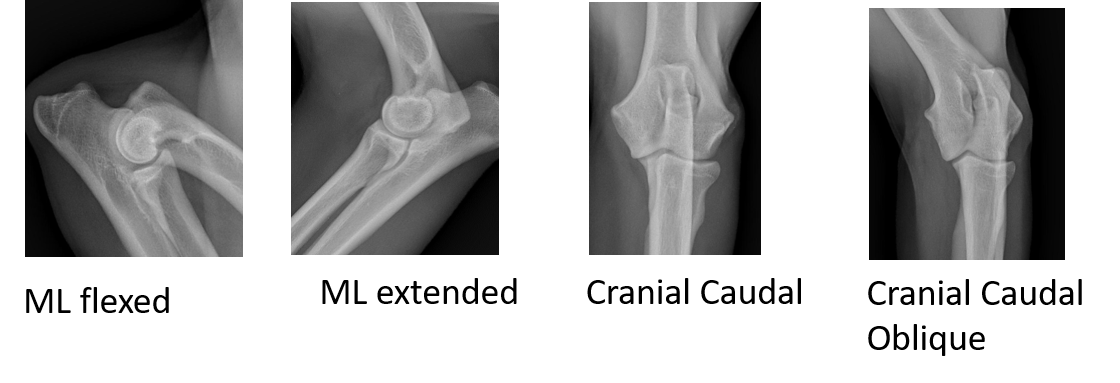

Elbow Dysplasia Screening Posted on March 9, 2020March 9, 2020 by sitemaster Behavior Career Outcomes Diagnoses Dog Data Genetic Tests Inbreeding Performance Reproduction Selection Behavior Career Outcomes Diagnoses Dog Data Genetic Tests Inbreeding Performance Reproduction Selection Search Impact Screening Scoring Selection Trends Impact Screening Scoring Selection Trends Screening [ninja_tables id="3944"] Best Views For Elbow Diagnoses Multiple diseasesBVA only 2 views4 views best practice [ninja_tables id="3987"] Search Impact Screening Scoring Selection Trends Impact Screening Scoring Selection Trends Screening [ninja_tables id="3944"] Best Views For Elbow Diagnoses Multiple diseasesBVA only 2 views4 views best practice [ninja_tables id="3987"]